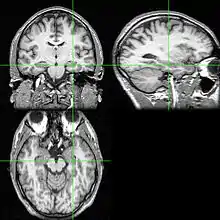

MRI scan of brain

An MRI scan with the hippocampus indicated in a coronal, lateral and horizontal view.